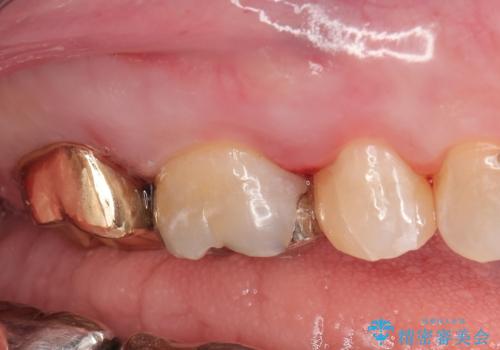

- 他院で右奥歯の治療が必要と言われて来院。

レントゲンと,CT撮影を行なったところ右上小臼歯が虫歯、右上第二大臼歯には根の先に大きな病気がありました。

手前の歯はセラミック治療を行い、奥の歯は精密根管治療を行いゴールドクラウンで治療を行いました。

セラミックインレーは古い材料を拡大鏡でしっかり取り除き適合の良い詰め物が装着されました。

根管治療はラバーダム防湿を行い、無菌的な状態で治療を行っています。

CTでは経過良好で経過観察を行なっていきます。